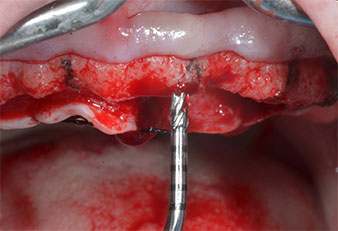

A causa dell'osso relativamente duro (D2) in quest'area, le sedi dell'impianto di 10 mm nelle posizioni 11 e 21 sono state finalizzate con un trapano rotante da 4 mm di diametro, in combinazione con un contrangolo chirurgico W&H WS-75 L, il motore per impianto W&H Implantmed e il modulo opzionale Osstell ISQ di W&H. Al contrario, a causa dell'osso morbido, le sedi posteriori sono state preparate a un diametro finale di 3 mm utilizzando lo strumento Piezomed I3P. Gli impianti sono stati infine posti per via transgengivale sull'osteointegrato per tre mesi (Figg. 6-10). La protesi dentaria esistente è stata mantenuta su quattro impianti provvisori (Fig. 8).